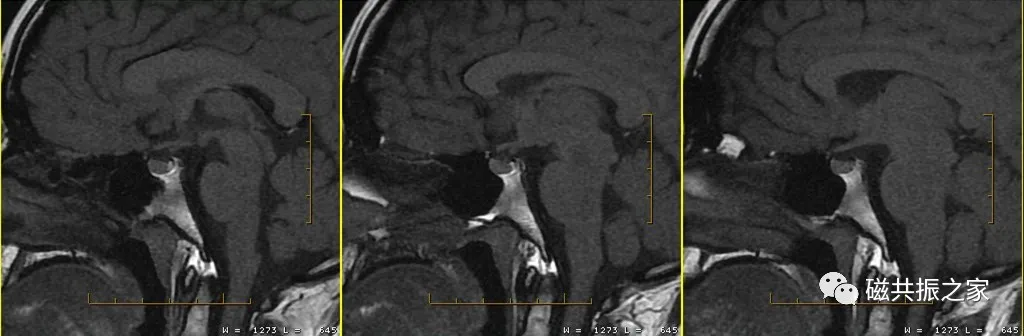

根据垂体的血供关系,垂体增强化顺序为垂体漏斗部及后叶、垂体柄、垂体前叶。

垂体无血-脑屏障,在注射造影剂后的早期即可发生强化,而大多数的微腺瘤由垂体的门脉系统供血,其强化比正常垂体慢,在注射造影剂后早期表现为弱强化或不强化,延迟期较正常垂体强化或不强化;但也存在少数的微腺瘤由颈内动脉直接供血,在增强早期也会发生强化。

据部分文献报道在注入对比剂早期即30-90S和1-3min为垂体微腺瘤的最佳对比时间。